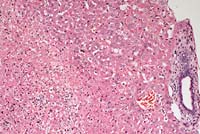

- Contributor's Diagnosis and Comments: Liver, hepatitis,

suppurative, with necrosis, multifocal, coalescing, severe, compatible

with Tyzzer's disease of neonatal foals.

- Intracellular bacteria compatible with Clostridium piliforme

(Bacillus piliformis) were demonstrated in histopathological

sections. Lesions and organisms are compatible with Tyzzer's

- Case 12-2a. Liver. Locally extensive hepatic necrosis

with an influx of neutrophils. 20X

AFIP Diagnoses:

- 1. Liver: Hepatitis, necrotizing, neutrophilic, acute, multifocal

to coalescing, random, severe, Quarter Horse, equine.

- 2. Liver: Cholestasis, canalicular, multifocal, moderate.

- Conference Note: Tyzzer's disease is an acute, highly

fatal, epizootic enterohepatic disease of neonatal or weanling

animals. It has been reported in numerous animal species, including

horses, cattle, mice, rats, hamsters, guinea pigs, rabbits, foxes,

and coyotes. The causative agent, Clostridium piliforme, is a

gram-negative, spore-forming, motile, obligate intracellular

bacterium with peritrichous flagella. The vegetative form causes

the disease state, and appears as bundles or "haystacks"

within its target cells, i.e. enterocytes and hepatocytes. Visualization

of the bacteria in histologic section is enhanced with silver

stains such as the Warthin-Starry procedure.